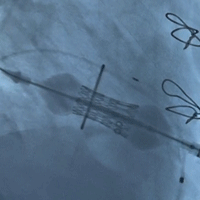

左室术后造影

(位置完美、无反流)